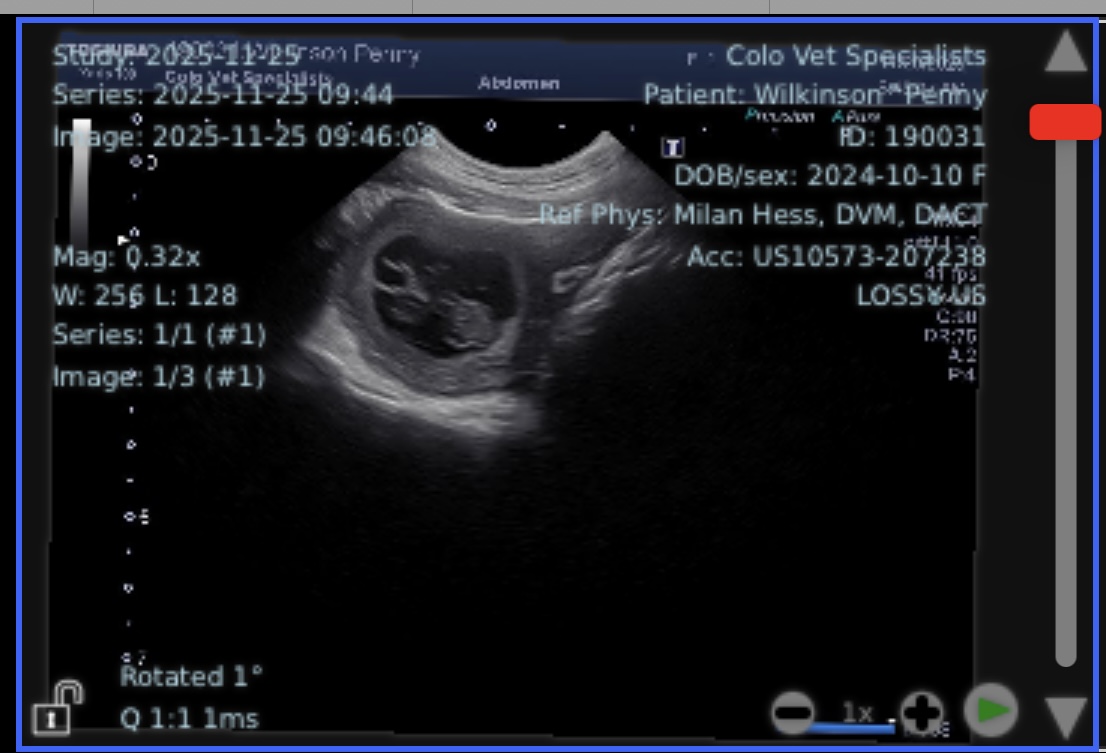

We have so much to be thankful for this season, and today we’re excited to share some wonderful news… our sweet Penny and Diego are expecting!

Puppies are due December 29th, and we could not be more thrilled. Penny has blossomed into such an intuitive, high-drive yet affectionate guardian, and Diego’s steady, gentle nature makes this pairing especially meaningful to us.